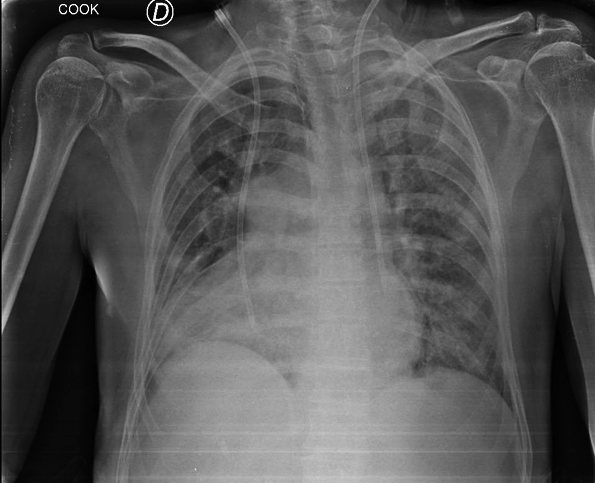

Presentamos un paciente con hiperamoniemia, que durante el estudio de la causa se diagnosticó agenesia de la vena porta, con anastomosis de la vena mesentérica a la vena renal izquierda. Ante el cuadro clínico y humoral, con compromiso neurológico, se decidió la colocación de un catéter doble lumen y se inició tratamiento mediante hemodiálisis convencional. Se colocó catéter por vía yugular izquierda presentando ubicación atípica y con mala cinética por lo que debió colocarse otro catéter doble lumen en vena subclavia derecha, ubicándose en posición convencional. La radiografía de control muestra la ubicación de ambos catéteres colocados.

Además de la anomalía vascular de la vena porta y de las cavidades cardíacas que presentes en este paciente, se detectó una anomalía vascular en las venas centrales. Se debe tener presente la posibilidad de que exista esta asociación de variantes anatómicas cuando debemos abordar vías centrales, en nuestro caso con catéter de doble lumen para tratamiento dialítico. El tip del catéter izquierdo se ubicó a nivel de seno coronario, donde el flujo sanguíneo resultó deficiente para efectuar el tratamiento dialítico. Se adjunta gráfico con esquema de las alteraciones más frecuentes de la vena cava superior doble.(1)

La TAC mostró una vena cava superior izquierda y otra derecha